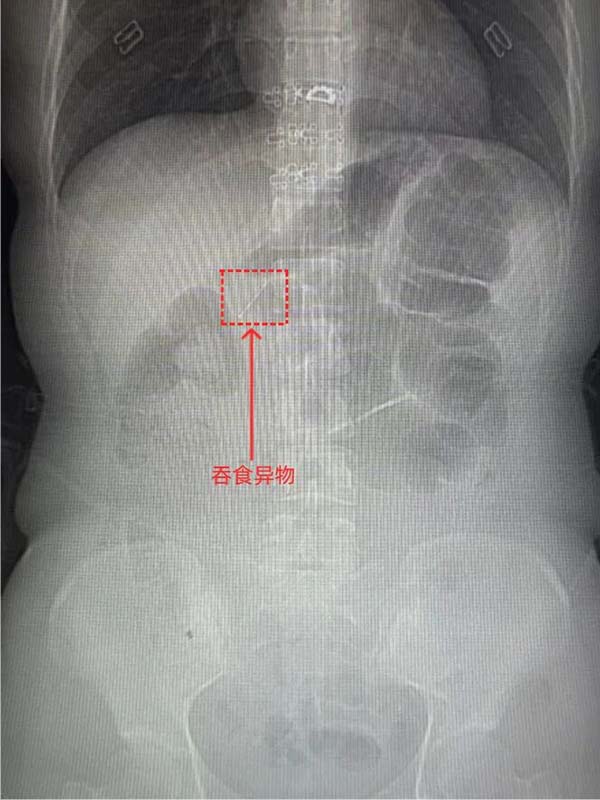

患者付某,女性,27岁,因“不慎吞食异物40分钟”于2025年12月23日18:04至中国中医科学院望京医院急诊外科就诊。患者无明显胸痛、腹痛、咽痛等不适。上腹、下腹、盆腔CT平扫:胃窦腔内细条形金属样高密度影,结合病史,考虑异物可能性大。与患者及家属充分沟通病情、交代内镜操作相关风险并获知情同意后,消化科牛然副主任医师带领内镜团队迅速为患者施行内镜下消化道异物取出术。镜下所见:进镜至十二指肠水平段时,于肠腔内探及一枚长约2厘米的金属细钉。该异物位置较深、形态细长,有坎顿、出血或穿孔的风险。幸运的是异物钳配合透明帽取出,过程顺利,所经过消化道粘膜观察无破损及划伤,患者无不适症状。

CT图

十二指肠水平部发现异物